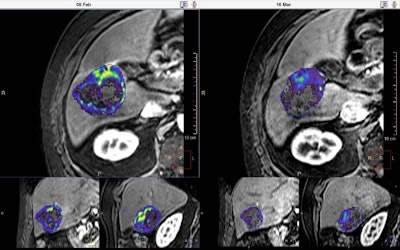

Oncologic image displayed on Philips IntelliSpace Portal 8.0 showing quantitative tumor viability (qEASL*) before and after transarterial chemoembolization (TACE). Much of the viable tumor (colored) becomes less enhanced (transparent) after the treatment.Researchers at Siemens have focused on the health economic aspects of the various imaging technologies, as well as on their diagnostic efficiency. At ECR 2016, the company is demonstrating the next phase in the development of its Teamplay IT solution for analyzing and optimizing the myriad work processes that are part of the routine daily work of all large hospital radiology departments.